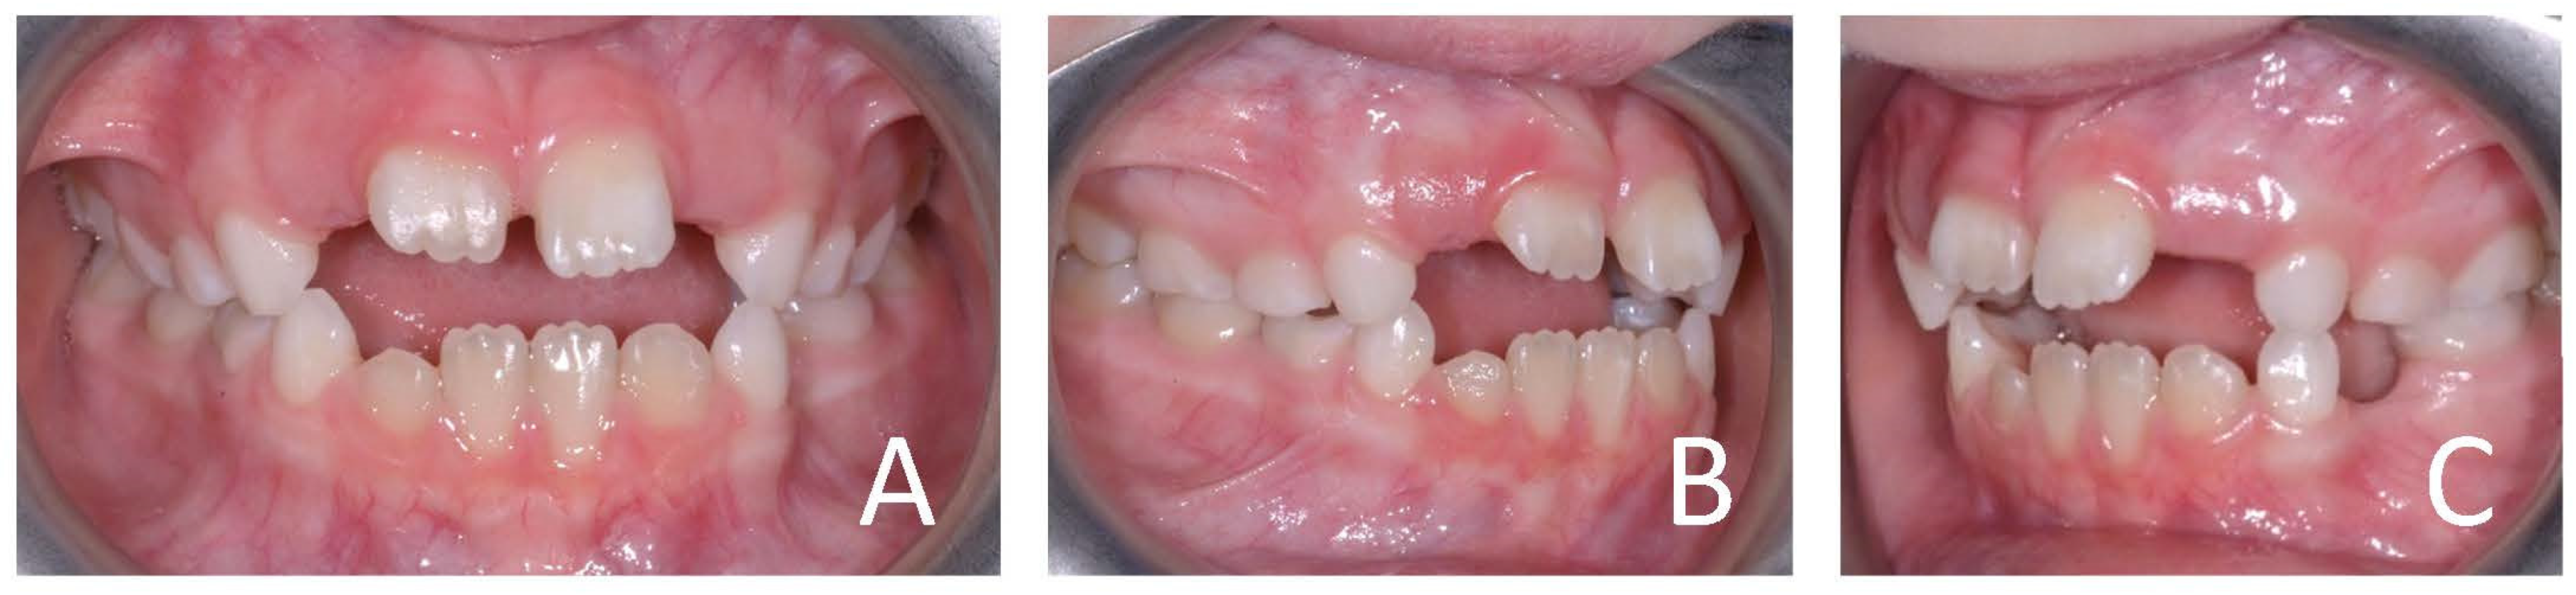

3.1. Clinical Case #1

| Cephalometric Analysis before Treatment | Val | Dev | Min | Med | Max | Diff |

|---|---|---|---|---|---|---|

| SNA | 82.4° | N | 80° | 82° | 84° | 0° |

| SNB | 74.7° | −xx | 78° | 80° | 82° | 3.3° |

| ANB | 7.7° | xx | 0° | 2° | 4° | 3.7° |

| sna-snp^Go-Gn | 23.2° | N | 15° | 20° | 25° | 0° |

| S-N^sna-snp | 10.6° | N | 7° | 10° | 13° | 0° |

| S-N^PO | 20.6° | xx | 11° | 14° | 17° | 3.6° |

| S-N^Go-Gn | 33.7° | N | 27° | 32° | 37° | 0° |

| SNBa | 127.1° | N | 124° | 129° | 134° | 0° |

| SND | 71.1° | −xx | 74° | 76° | 78° | 2.9° |

| IS^II | 103° | −xxxxx | 125° | 130° | 135° | 22° |

| IS:N-A | 2.9 | −x | 3 | 4 | 5 | 0.1 |

| II:N-B | 4.8 | N | 3 | 4 | 5 | 0 |

| II:A-Pog | 0.8 | N | −1 | 1 | 3 | 0 |

| Ls:Line S | 2.6 | xx | −1 | 0 | 1 | 1.6 |

| Li:Line S | 0.6 | N | −1 | 0 | 1 | 0 |

| Cvm:S-Gn | −3.3 | −xxx | −1 | 0 | 1 | 2.3 |

| Mol Sup^P. Occl | 109° | xxx | 88° | 90° | 92° | 17° |

| N-S-Cop | 118.3° | N | 117° | 122° | 127° | 0° |

| S-Cop-Go | 156.4° | xx | 137° | 143° | 149° | 7.4° |

| Cop-Go-Gn | 119° | N | 115° | 120° | 125° | 0° |

| Cop-Go-N | 48.5° | N | 48° | 50° | 52° | 0° |

| N-Go-Gn | 70.5° | N | 68° | 70° | 72° | 0° |

| II^Go-Gn | 104.1° | xxx | 92° | 93° | 94° | 10.1° |

| SOr:sna | 57.5 | 0 | 0 | 0 | 57.5 | |

| sna:Me | 54.1 | 0 | 0 | 0 | 54.1 | |

| S:N | 63.2 | −xxx | 71 | 74 | 77 | 7.8 |

| snp:A | 44.4 | 0 | 0 | 0 | 44.4 | |

| Go:Me | 59 | −xxx | 69.3 | 74.3 | 79.3 | 10.3 |

| Wits | 4.2 | xx | −2 | 0 | 2 | 2.2 |

| IS^N-S | 119.1° | xxx | 101° | 103° | 105° | 14.1° |

| Pog:N-B | 1.6 | 0 | 0 | 0 | 1.6 | |

| Pog:N-B—II:N-B | −3.2 | - | 0 | 0 | 0 | 3.2 |